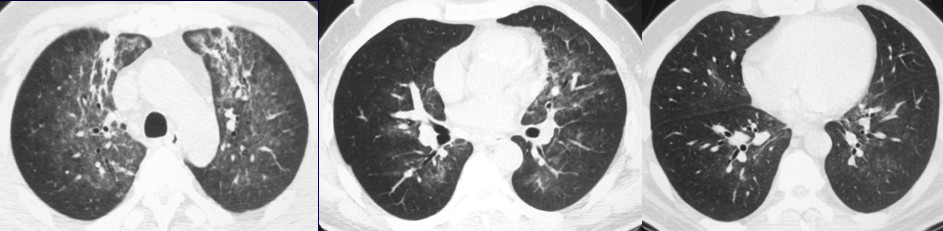

磨玻璃影

两肺弥漫的磨玻璃影在鉴别诊断中比较麻烦,因为它涉及的病变很多,形态也差不多。X线平片可以正常或仅呈淡云雾状影,但是CT比较明确,肺密度增高影但不掩盖其中的血管影。

两肺弥漫磨玻璃影的常见病因,感染方面主要是病毒性肺炎、PCP,这两种疾病的主要表现为两肺磨玻璃影,一部分支原体肺炎也可以表现为磨玻璃影,但很少两肺对称,一般不对称或者是一个肺叶或两个肺叶的改变。对于非感染病变来说,包括ARDS、AIP、肺水肿、肺出血、急性嗜酸性细胞肺炎、放射性肺炎。

病例1:PCP

这是一个47岁男性患者,发烧。X线胸片显示两上肺有些实变,仔细看在肺门周围有淡淡的密度增高。CT显示上肺实变影,在肺门周围及更低的层面都可以看到磨玻璃影,下肺相对较少,两肺病变以磨玻璃影为主。如果发烧的病人出现这种改变首先考虑病毒性肺炎和PCP,但病毒性肺炎往往在下肺多一些。所以对于这个病人而言,放射科怀疑PCP并提醒临床检查HIV,结果为HIV阳性,后来诊断为卡氏肺孢子虫肺炎。

病例2:吸入性肺炎

这是一个89岁的老年男性,低烧。胸片显示淡淡的密度增高阴影,但CT很明确的显示为两肺磨玻璃影,在两下叶肺门后区域,中叶比较贴近叶间裂的位置。对于这样的位置,考虑吸入性肺炎,但是肺水肿也可以表现为两肺密度增高、磨玻璃影,通过追问病史发现病人因为喝水呛到了,所以诊断就比较简单。

当两肺对称的弥漫性磨玻璃影,在鉴别诊断时除了考虑病毒性肺炎或卡氏肺孢子虫肺炎,还有肺出血、肺水肿,这几种疾病在影像学上可以一模一样,但是临床表现明显不同,较容易鉴别。

病例3:弥漫性肺泡出血

女性,45岁,胸闷咳血。影像学表现比较典型,两肺磨玻璃影,外周无小叶间隔增厚,另外未见胸水。